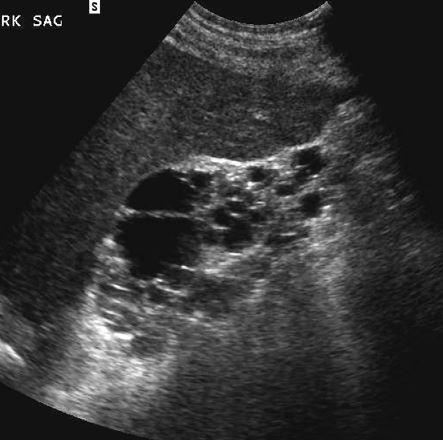

Acquired cystic disease of the kidneys

NOTE: atrophic, echogenic kidneys!!!

vs inherited polycystic kidney disease!!!